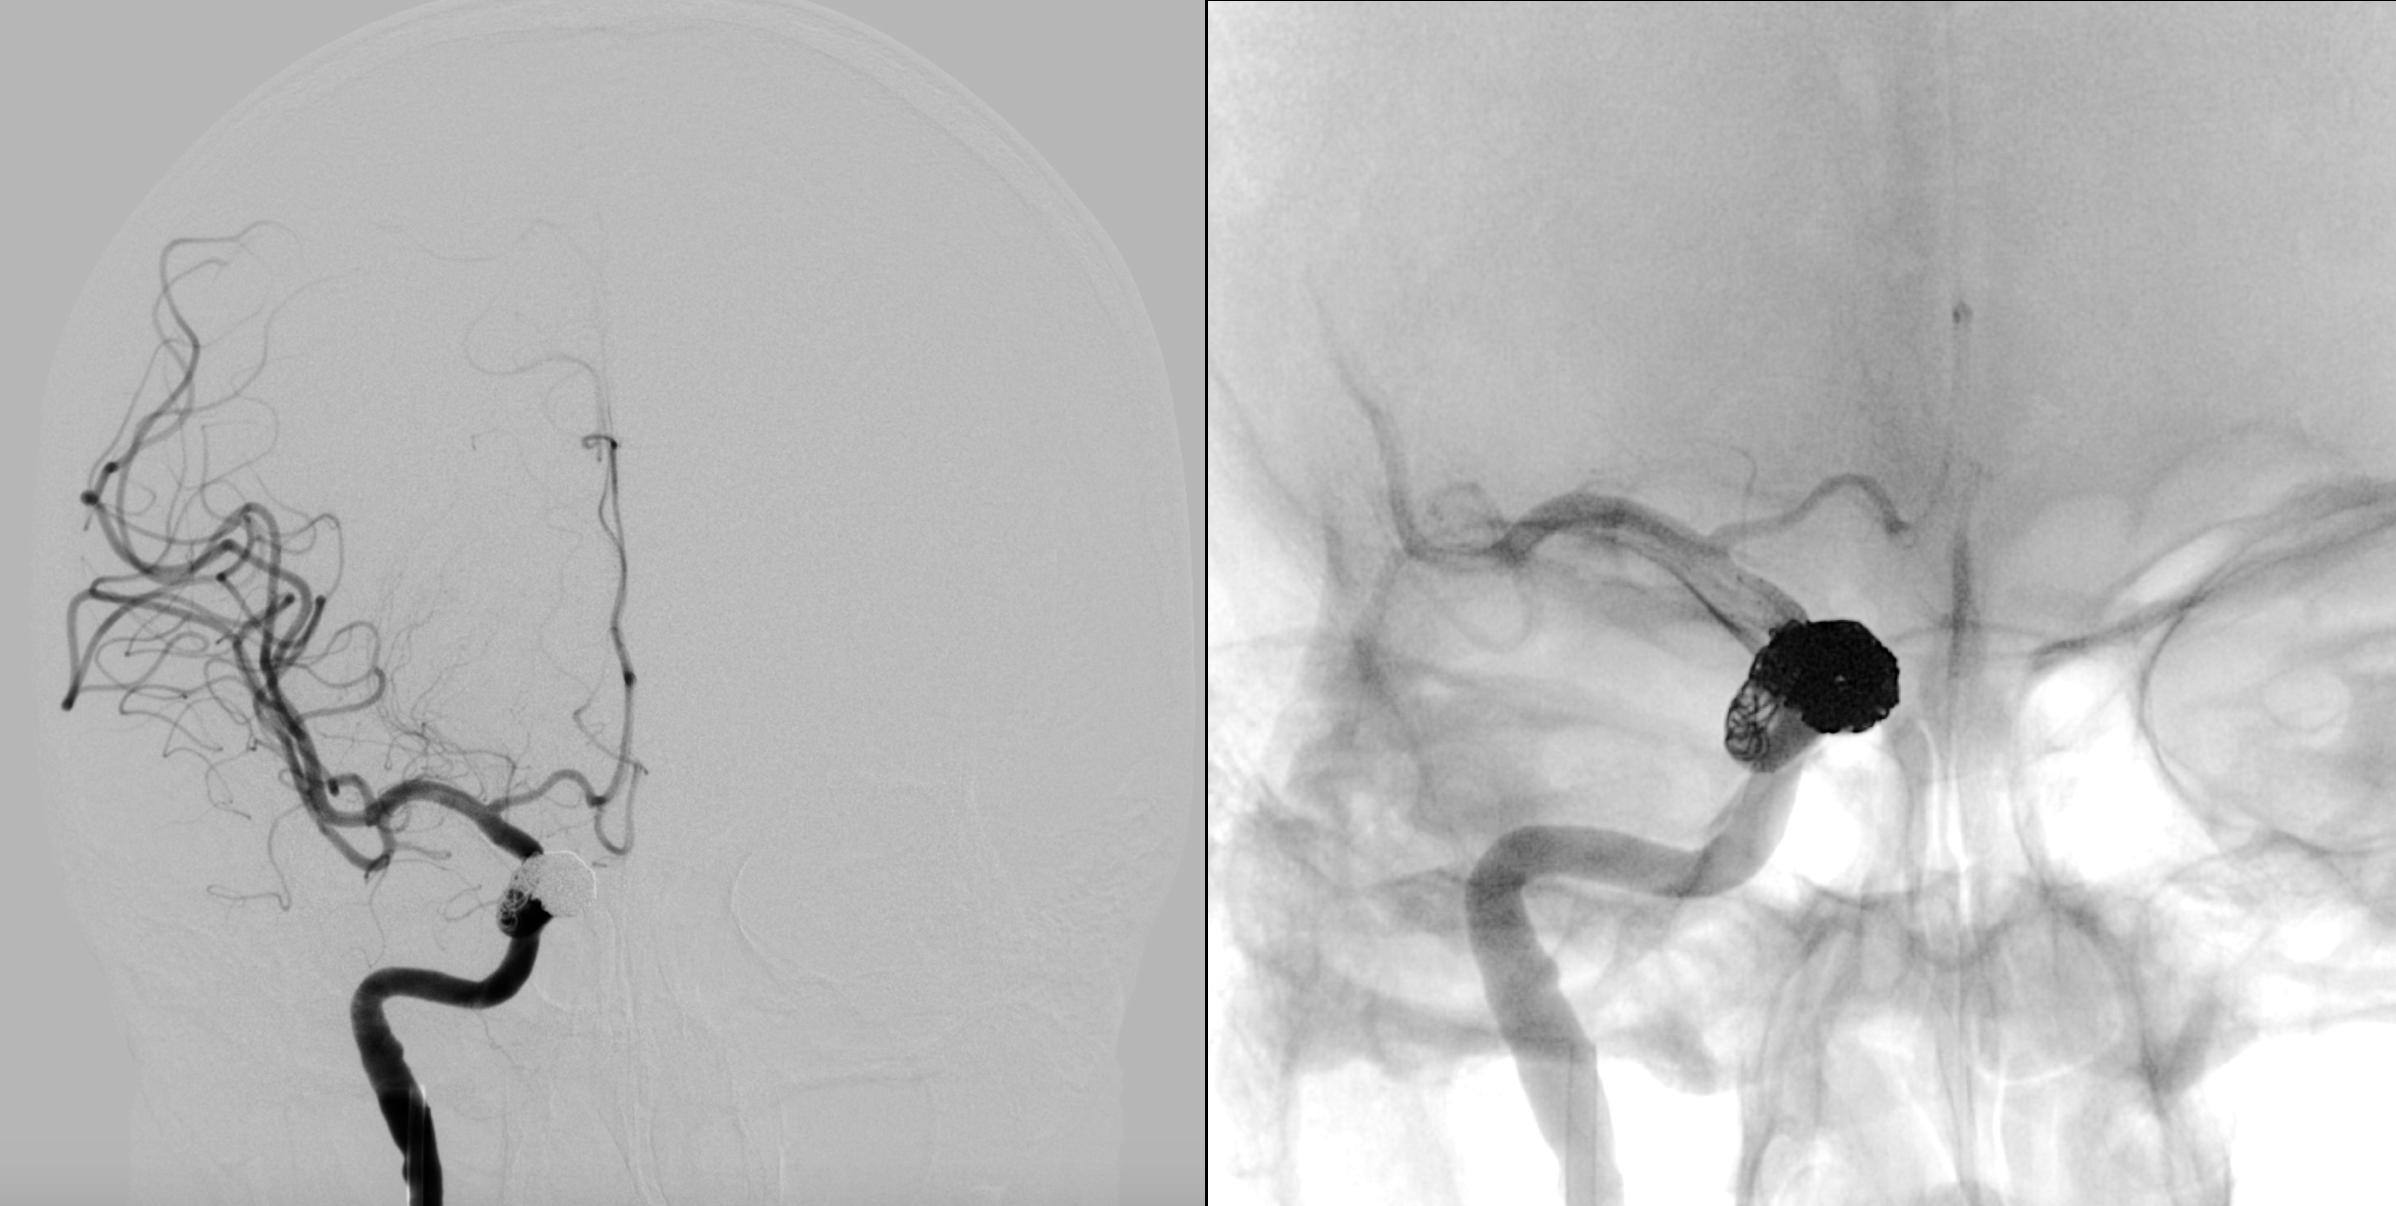

不同工作位造影:动脉瘤完全栓塞,载瘤动脉通畅。

术后正位造影及蒙片显示:动脉瘤完全栓塞!

术后侧位造影及蒙片显示:动脉瘤完全栓塞!

蒙片显示:支架贴壁良好!部分弹簧圈被支架贴附于近端瘤颈及正常颈内动脉内壁!